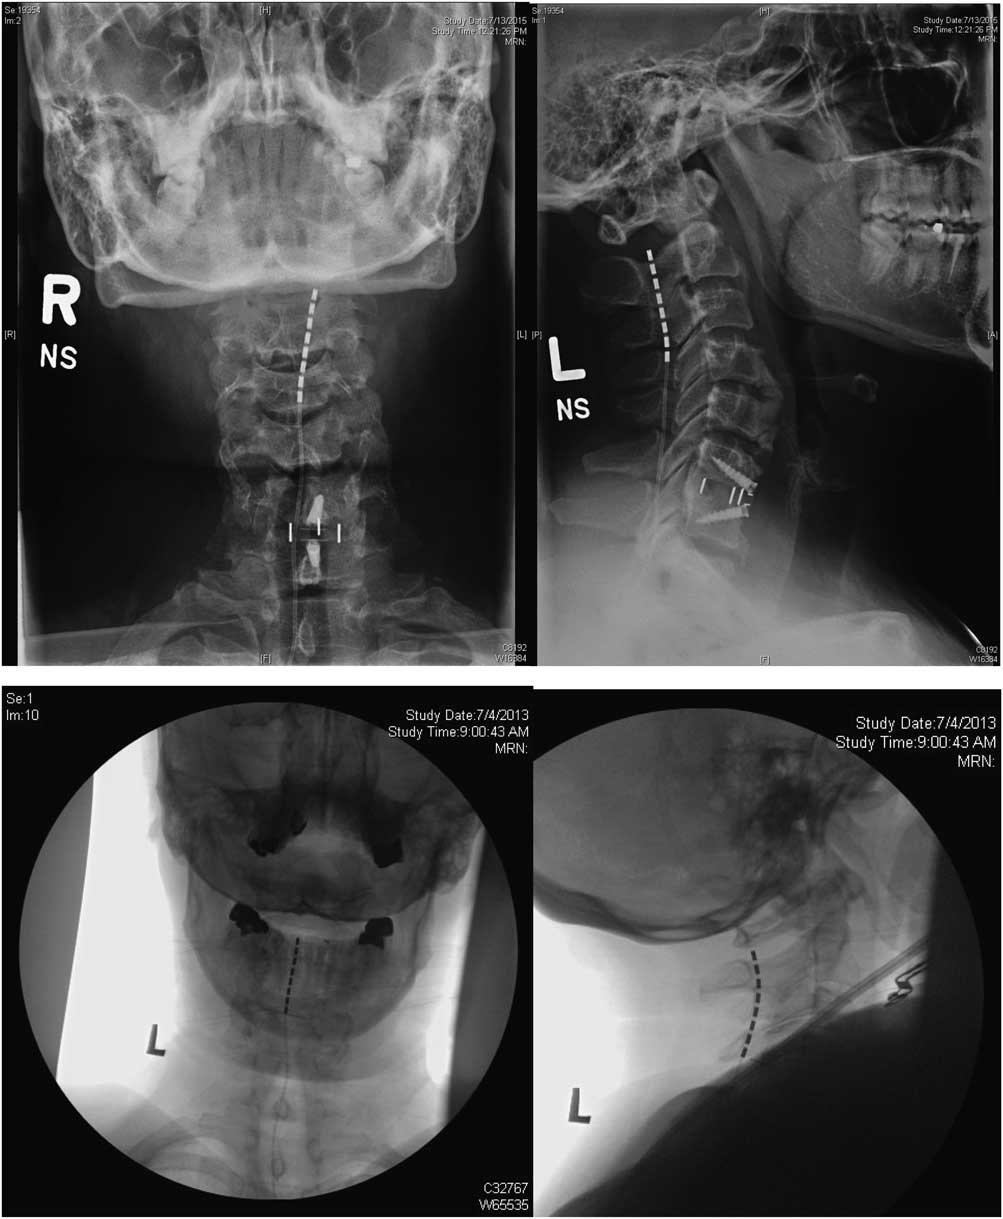

Treatment involved a trial period of 3 weeks, during which the programming of the device was adjusted and the patient’s response to the therapy was monitored. The trial electrodes were then removed and there was a mandatory washout period of at least two weeks. Permanent implantation followed successful trials, defined as a visual analogue scale (VAS) decrease ≥50% or a sufficiently large pain reduction to have a significant effect on the patient’s quality of life. The stimulation technique was chosen was based the geographic distribution of the pain as well as intraoperative test stimulation results. In general, for the upper limb, nerve root stimulation was used in patients where the pain area was limited to one to four dermatomes. Electrodes were anchored to the thoracolumbar fascia using the standard technique with Boston Scientific’s Clik anchors. Examples of the placement of SCS and DNRS electrodes in the cervical spine are shown in Figures 1 and 2, respectively.

Figure 1 Anteroposterior and lateral X rays for two patients showing placement of SCS electrodes.